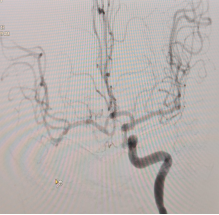

术后即刻正侧位,显示血管再通良好

病情危重,征得家属同意后,桥接脑血管介入治疗。在局部麻醉下,经右侧股动脉穿刺行经皮颅内动脉取栓术,术中取出约8mm质硬血栓,恢复血管再通。

术后即刻NIHSS评分3分,24小时后NIHSS评分1分,术后2天下地行走,术后4天复查影像学正常,出院时NIHSS0分,日常生活自理,言语清晰,肢体活动如常。